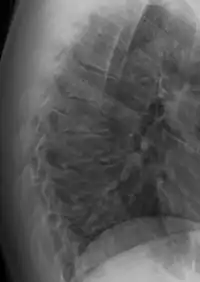

Scheuermann's disease on lateral Xray of the T spine

Scheuermann's disease is a self-limiting skeletal disorder of childhood. Scheuermann's disease describes a condition where the vertebrae grow unevenly with respect to the sagittal plane; that is, the posterior angle is often greater than the anterior. This uneven growth results in the signature "wedging" shape of the vertebrae, causing kyphosis. It is named after Danish surgeon Holger Scheuermann.[3][4][5]